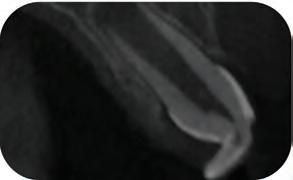

Periapical X-ray confirmed the findings of the clinical examination and root caries was also detected in the distal root of tooth #46, which answered positively to the sensitivity test (Fig.1-2).

The treatment plan began with a focus on returning the patient to adequate periodontal health. In a subsequent session, with improved condition of the periodontium, the restoration of tooth #46 was performed. Under block anesthesia of right inferior alveolar nerve and rubber dam isolation, the amalgam restoration was completely removed and access to the caries cavity obtained (Fig. 3-5). Despite the proximity to the pulp tissue, no exposure occurred, and the class II cavity was fully restored with Biodentine™ (Fig. 6-8).

At two months’ follow-up, no symptoms were reported, no periapical lesion was observed radiographically, and the clinical examination showed normal vitality (Fig. 9-10). Thus, it was decided to perform the definitive restoration, leaving Biodentine™ as the definitive base.

Fig. 1: Initial clinical situation.

Fig. 2: Initial X-ray.

Fig. 3: Class II cavity prepared.